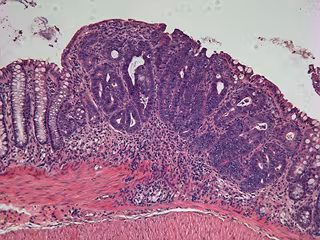

Tumor de colon. Cáncer.

Tumor de colon. Cáncer. - IRB - Archivo